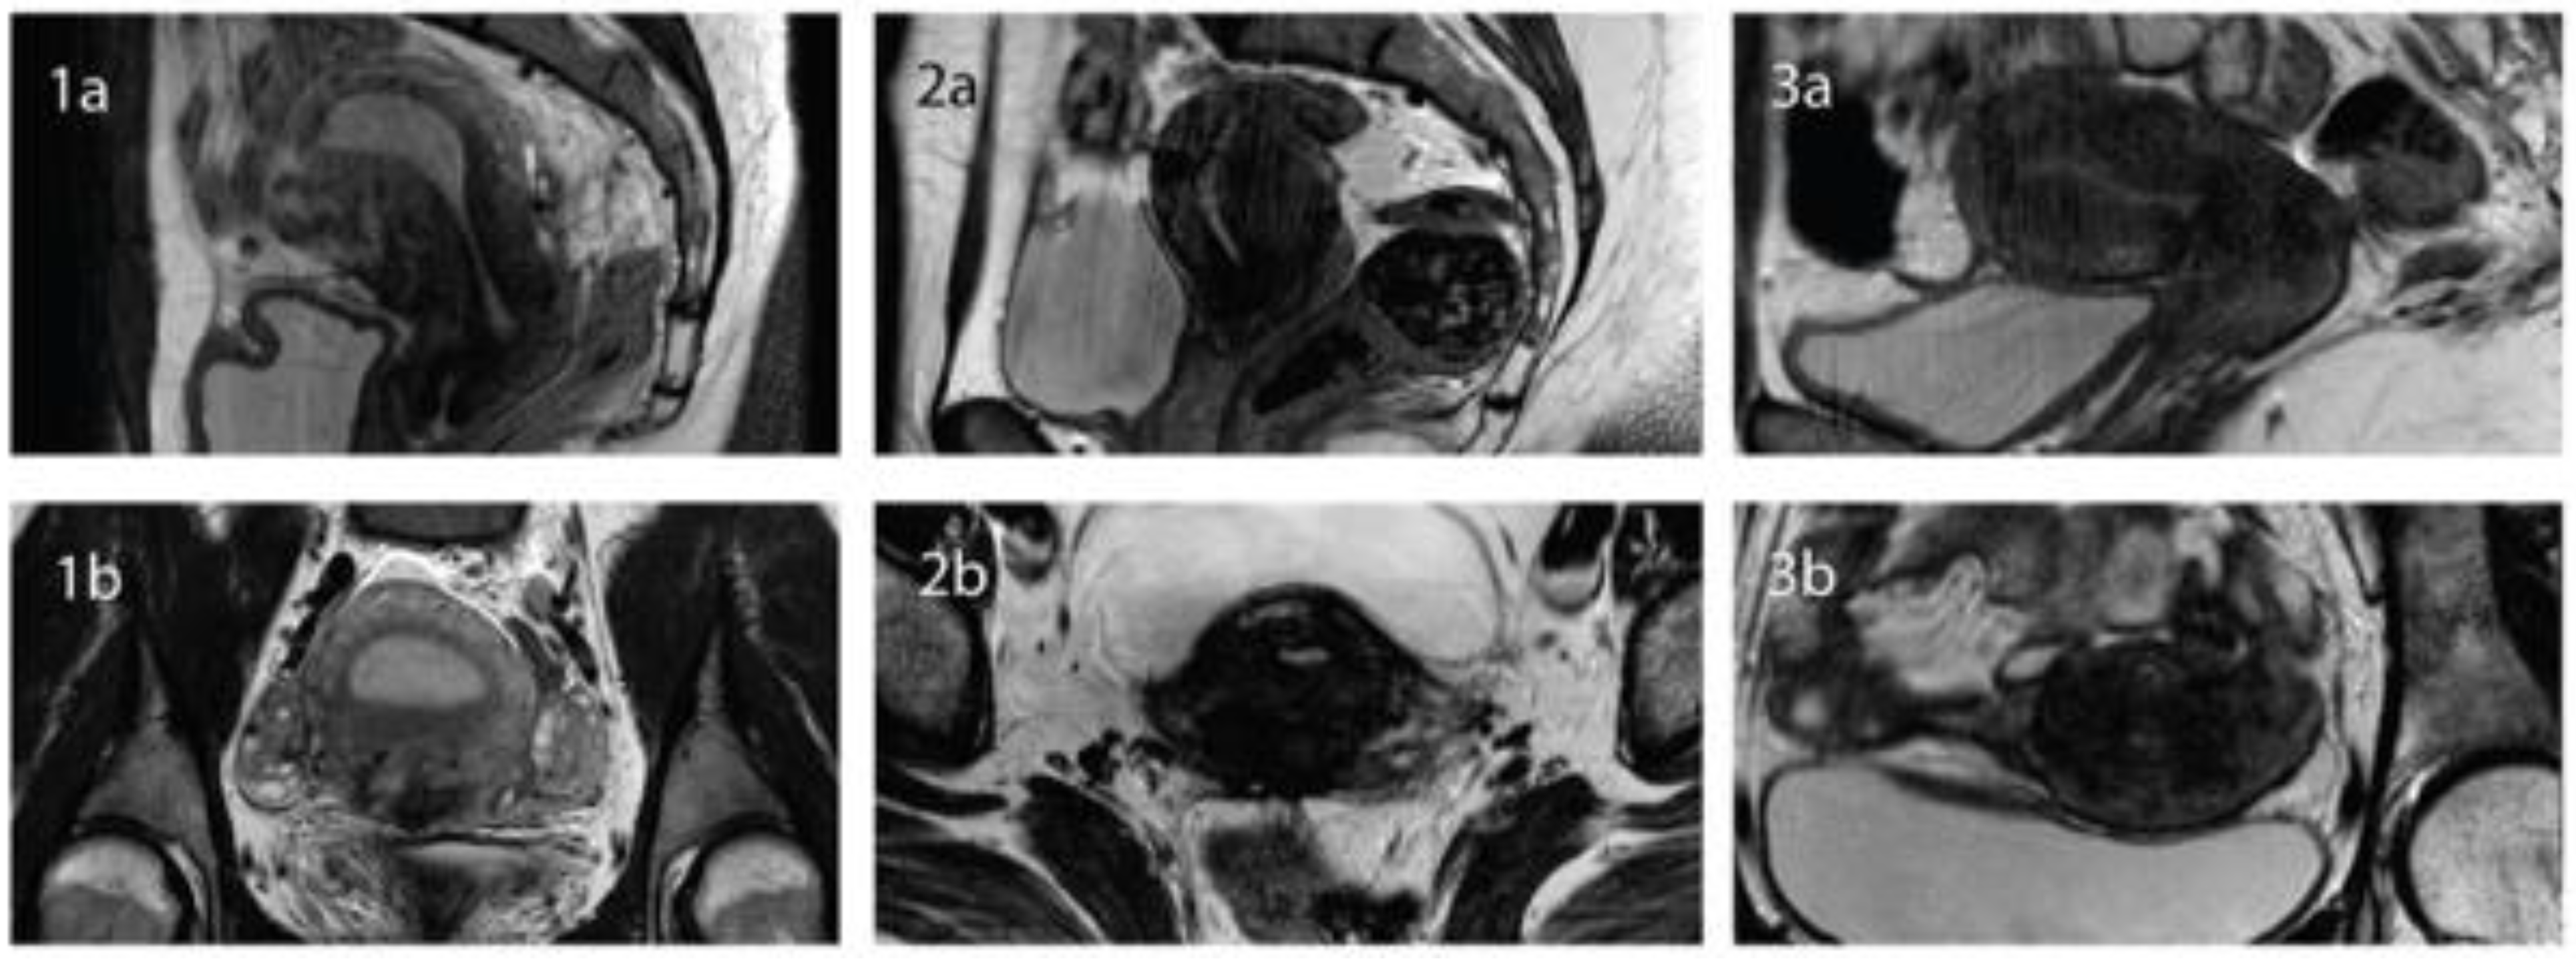

2.2. MRI Examination

2.3. Diagnostic Criteria